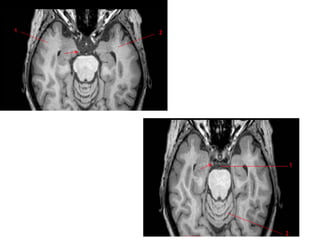

LocaHon	of	lesion?

---Lesion	in	front	of	parieto-occipital	sulcus	so	answer	is

posterior	parietal	lobe.

Next	quesHon	?

--Answer	is	Cuneus	gyri	of	Occipital	lobe.

Next	QuesHon?

Lesion	is	above	the	sylvian	fissure	and	in	front	of	central

sulcus	So	answer	is	posterior	frontal	lobe.

Next	QuesHon